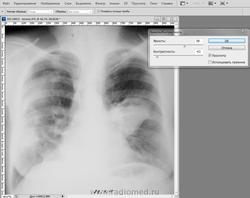

Вот такая кака в исходном виде:

***с помощью автотона:

***но порой автотон делает фото вообще не смотрибельным, тогда так: уровни:

***затем кривые:

***затем яркость-контрастность: